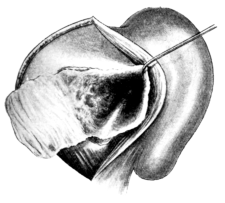

| 228. | Post-meatal Skin Flaps | 401 |

| 229. | Post-meatal Skin Flaps | 401 |

| 230. | Closure of Wound after ‘Radical’ Mastoid Operation | 401 |

| 231. | Körner’s Post-meatal Flap | 402 |

| 232. | Panse’s Post-meatal Flap | 402 |

| 233. | Stacke’s Post-meatal Flap | 402 |